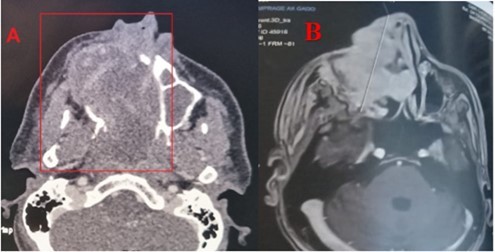

Patient aged 40 years without any surgical medical history who consults at our level in 2022 for a right epistaxis of average abundance with nasal obstruction and an induration next to the maxillary sinus right to palpation. Endoscopy revealed a reddish polypoid mass filling the right nasal cavity without palpable cervical adenopathies, CT returned in favor of an expansive tissue process of the right maxillary sinus, extended to the soft parts and the homolateral nasal cavity. The complete resection of the mass was performed by endonasal surgery (endoscopic maxilectomy). The histological examination found hemangioendothelioma without signs of malignancy with infiltrated margins, external complementary radiotherapy was indicated (50 Gy, 2Gy per day for 5 days a week on the maxillary sinus), a radiological check (MRI) 4 months later does not find any residual tumor. After an absence of 15 months, the patient revisits for resumption of symptomatology with right epistaxis of great abundance requiring 2 globular units, a reddish mass protruding from the nasal vestibule, lysing the bony palate with extension towards the cheek (Figure 1) and alteration of the CT and MRI find an expansive tumor process centered on the nasal cavity and maxillary sinus right of 103x 58 x41 vs 156x67x95mm with currently highly elevated spans, the process is globally hypodense and weakly elevated, presence of some vessels as well as hypervascular portions of peripheral localization at the extended jugal level and in front of the internal canthus, bone palace lysis, with a negative extension balance (Figure 2).

Figure 2.CT scan with PC injection (A) and MRI in axial sections (B) showing the lesion of the right maxillary sinus extended to neighboring structures

Angiosarcoma is a very rare malignant tumour that accounts for about 1 to 2% of all sarcomas 1. Nasosinusial localization is exceptional: 4% of angiosarcomas occur in the pharynx, oral cavity or sinuses 8; only 24 cases have been reported from 1974 to 2009 9. The age range varied between 8 and 81 years, our patient was 40 years old, with a male predominance (16 men for 8women in the 24 cases reported), which was the case with our patient 10. The etiopathogenesis of angiosarcomas is not known, radiation exposure presents a risk up to seven times greater for secondary angiosarcoma 9, vinyl chloride, arsenic and thorium dioxide, which could cause lymphedema, would cause angiosarcoma 11 in our patient, where there was secondary sarcomatous transformation after irradiation. The clinical presentation of angiosarcoma is generally mild in the initial phase 6. The macroscopic aspect is unspecific 12. It comes in the form of polyps or red or purplish plaques sometimes taking the appearance of a hematoma. This misleading clinical aspect requires follow-up and biopsy at the slightest doubt. Our patient had unilateral nasal obstruction with epistaxis of small abundances and smooth reddish mass in the nasal cavity and, at a later stage, the tumor syndrome becomes evident (epistaxis of great abundance, blocked nose, alteration of the general condition) with extension to surrounding structures (eyeball, palate, skin). The radiological presentation is extremely variable and not very specific. On imaging, the tumour has variable dimensions (ranging from 2 to 8 cm in published cases) with hypervascular lesion, heterogeneous contrast uptake and signs of bone lysis on CT scan, and can be evaluated for its extent. In MRI, the tumour has a low-intensity signal on T1 weighted sequences and a high-intensity heterogeneous signal on T2-weighted sequences with an enhancement of intense and heterogeneous contrast 4. The diagnosis of certainty is established by histopathological staining and confirmed by immunohistochemistry 1, 3. Three microscopic aspects have been described: fusiform cells of the epithelioid type and of the undifferentiated or solid type. In undifferentiated forms, the vascular marker CD31 is useful for diagnosis. Other less specific or sensitive markers may be used (Willebrand factor, CD34, lectins) 9. Epithelioid forms pose the problem of differential diagnosis with poorly differentiated squamous cell carcinomas, especially since there is a strong expression of AE1/AE3 cytokeratins in angiosarcoma. In the present case, fusiform cells with CD31 positive vascular markers were found to support the diagnosis of fusiform angiosarcoma NOS 13. Differential diagnosis includes hemangioma, intravascular papillary endothelial hyperplasia (Masson disease), juvenile nasopharyngeal angiofibroma, hemangiopericytoma, Kaposi sarcoma and malignant melanoma 14. The prognosis of these tumours remains bleak today. At five years, there are between 30 and 45% survivors in the localized stage 15. The main prognostic factors are a pejorative size greater than five centimeters; in our patient, the mass has reached 10 cm, a high histological grade, an age greater than 70 years. Resectability, non-RO surgery, and absence of multimodal treatment 16. The treatment is based on surgery (adapted to tumor location and extension) followed by radiation therapy. Other treatment modalities have been tried, such as chemotherapy, radiosurgery (gamma knife) 11, and interleukins 17; and trials with propranolol are currently underway 18. However, no standardized therapeutic management has been defined given the limited number of published cases and the absence of comparative studies. Five-year survival is 22% (versus 12% for soft tissue angiosarcoma in the head and neck) and depends on the degree of tumor differentiation and stage at diagnosis 19. Distant metastases may occur in 30% of cases within the first 24 months; metastases involve bones, lungs, liver, skin or cervix 10.